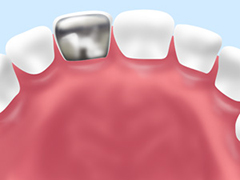

銀歯とセラミックの比較

保険診療のむし歯治療ではレジン(歯科用プラスチック)や金銀パラジウム合金が使われます。レジンは、白っぽい色なのであまり目立ちませんが、経年により着色していきます。金銀パラジウム合金とはいわゆる「銀歯」で白い歯列の中で黒く見えて目立ちます。銀歯のデメリットは目立つだけではありません。経年により少しずつ金属がイオン化して溶け出し、体内に吸収されると全身に金属アレルギーの症状が現れることがあります。また歯ぐきの黒ずみの原因にもなるのです。

むし歯治療の際におすすめの素材はセラミックです。

天然歯に近い仕上がりになるだけでなく、汚れがつきにくいので、むし歯や歯周病になるリスクを抑えることができます。

金銀パラジウム合金

保険診療用の奥歯のクラウンです。インレーにも使用します。